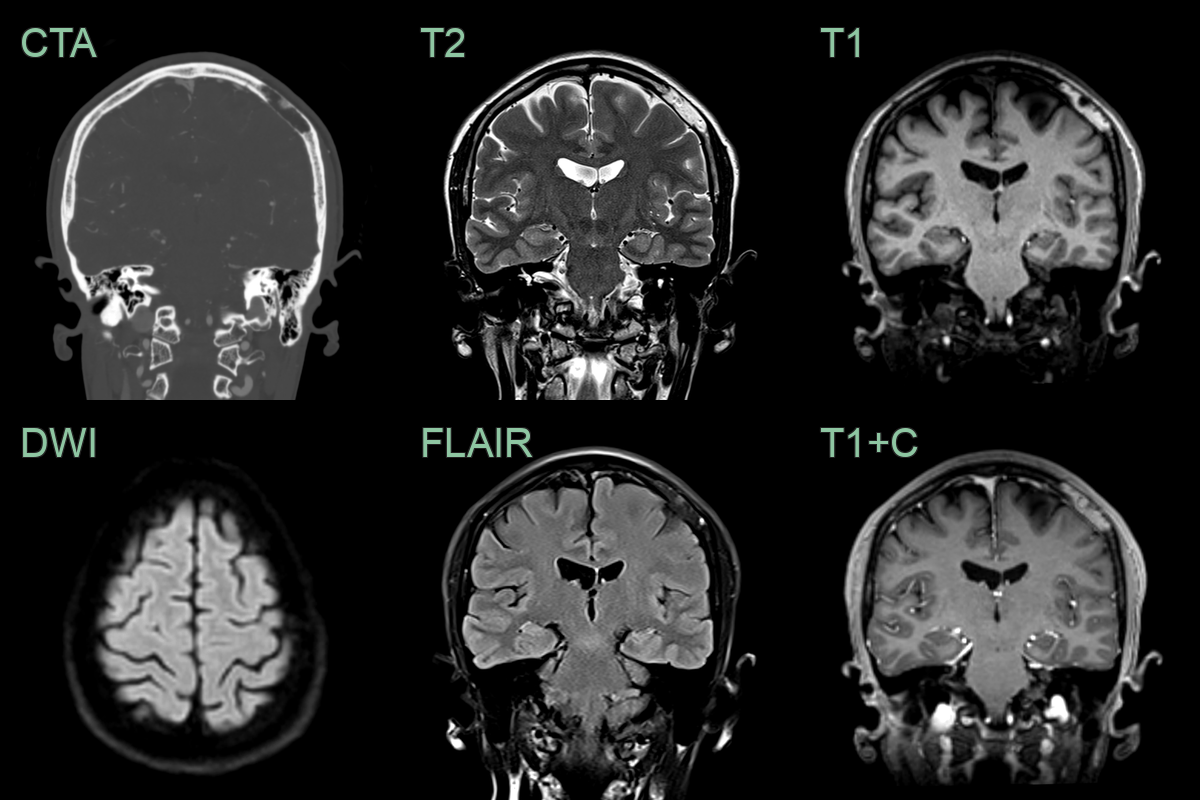

• A 70-year-old patient presented with a lump near the left zygoma.

• MRI showed an avidly enhancing lesion replacing part of the frontal bone without significiant avidity on FDG PET.

• Histopathology following resection (due to slow enlargement) confirmed a hemangioma.